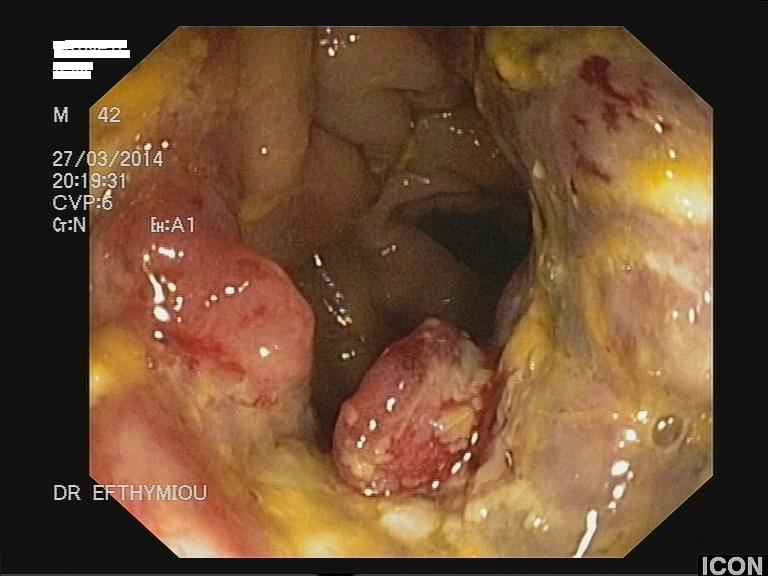

Άνδρας 43 ετών, χωρίς προηγούμενο ατομικό ή οικογενειακό ιστορικό, εμφάνισε επίμονους εμέτους και επιγαστραλγία. Υποβλήθηκε σε αξονική τομογραφία θώρακος, άνω και κάτω κοιλίας από το θεράποντα ιατρό του που έδειξε διάχυτη θωρακική και κοιλιακή λεμφαδενοπάθεια, με διογκωμένους λεμφαδένες στον υποτροπιδικό χώρο, στον αλλήρειο τρίποδα, στον ηπατοδωδεκαδακτυλικό σύνδεσμο και πέριξ του παγκρέατος. Ο ασθενής παραπέμφθηκε για ενδοσκοπικό υπέρηχο και λήψη βιοψιών από τους λεμφαδένες. Έγινε βιοψία με ειδική βελόνα για λήψη ιστοτεμαχίων (Pro-Core 19g) από λεμφαδένες σε 3 διαφορετικές θέσεις (υποτροπιδικά, αλληρείου τρίποδα και ηπατοδωδεκαδακτυλικού συνδέσμου). Η ιστολογική εξέταση και ο ανοσοϊστοχημικός έλεγχος έδειξε αδενοκαρκίνωμα χαμηλής διαφοροποίησης χωρίς θετικότητα στις επιμέρους, ειδικές χρώσεις. Ο ενδοσκοπικός έλεγχος του πεπτικού επιβεβαίωσε την ύπαρξη νεο-εξεργασίας στην ηπατική καμπή του παχέος εντέρου που ιστολογικά ήταν ένα αδενοκαρκίνωμα χαμηλής διαφοροποίησης. Ο ασθενής παραπέμφθηκε για προεγχειρητική χημειοθεραπεία και χειρουργική αντιμετώπιση.

Μάζα παχέος εντέρου στην κολονοσκόπηση